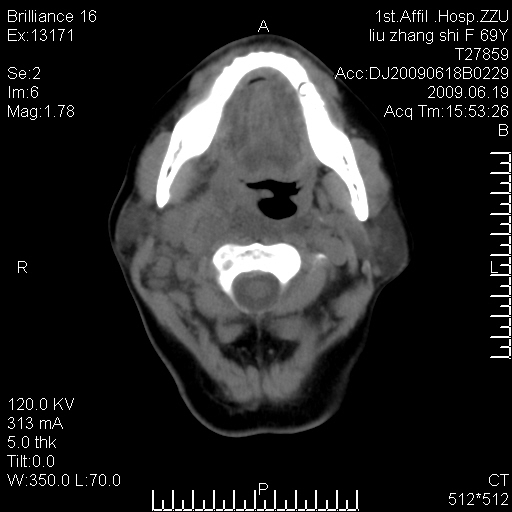

标题: CT26782:女,69岁,颈部占位,3天后公布病理结果。

【病理证实系列】女,69岁,颈部占位,有病理结果,3天后公布。(由于病例时间较久,临床资料不全,请网友见谅)本系列将有几百种常见、少见及罕见病例,均经病理证实。病例资料来自郑州大学第一附属医院。与网友共享,本人有空就发。

甲状腺癌并颈部淋巴结转移。感谢楼主的良苦用心,谢谢。

甲状腺癌并颈部淋巴结转移。

需与鼻咽癌鉴别!

支持甲状腺癌广泛侵及周围结构并颈部淋巴结转移。

鉴别:淋巴瘤、恶性神经源性病变、恶性纤维组织细胞瘤。

病理结果:颈部非霍奇金淋巴瘤。